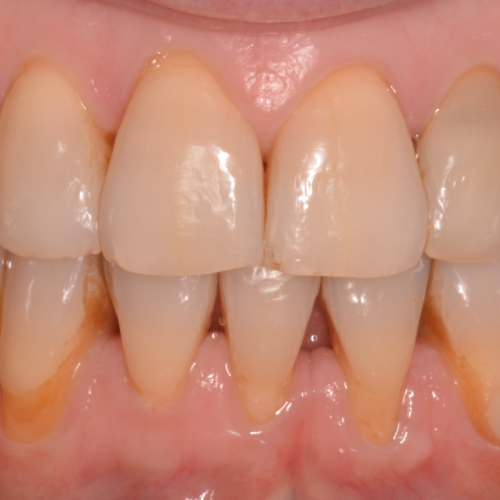

Cirugías de injertos

Existen cantidad de técnicas y biomateriales destinados a restauras los tejidos peridodos. Estos tejidos pueden ser tanto hueso como la encía que lo cubre. Se pueden reponer estos tejidos perdidos con injertos del propio paciente (autólogos) o con materiales sintéticos (biomateriales).